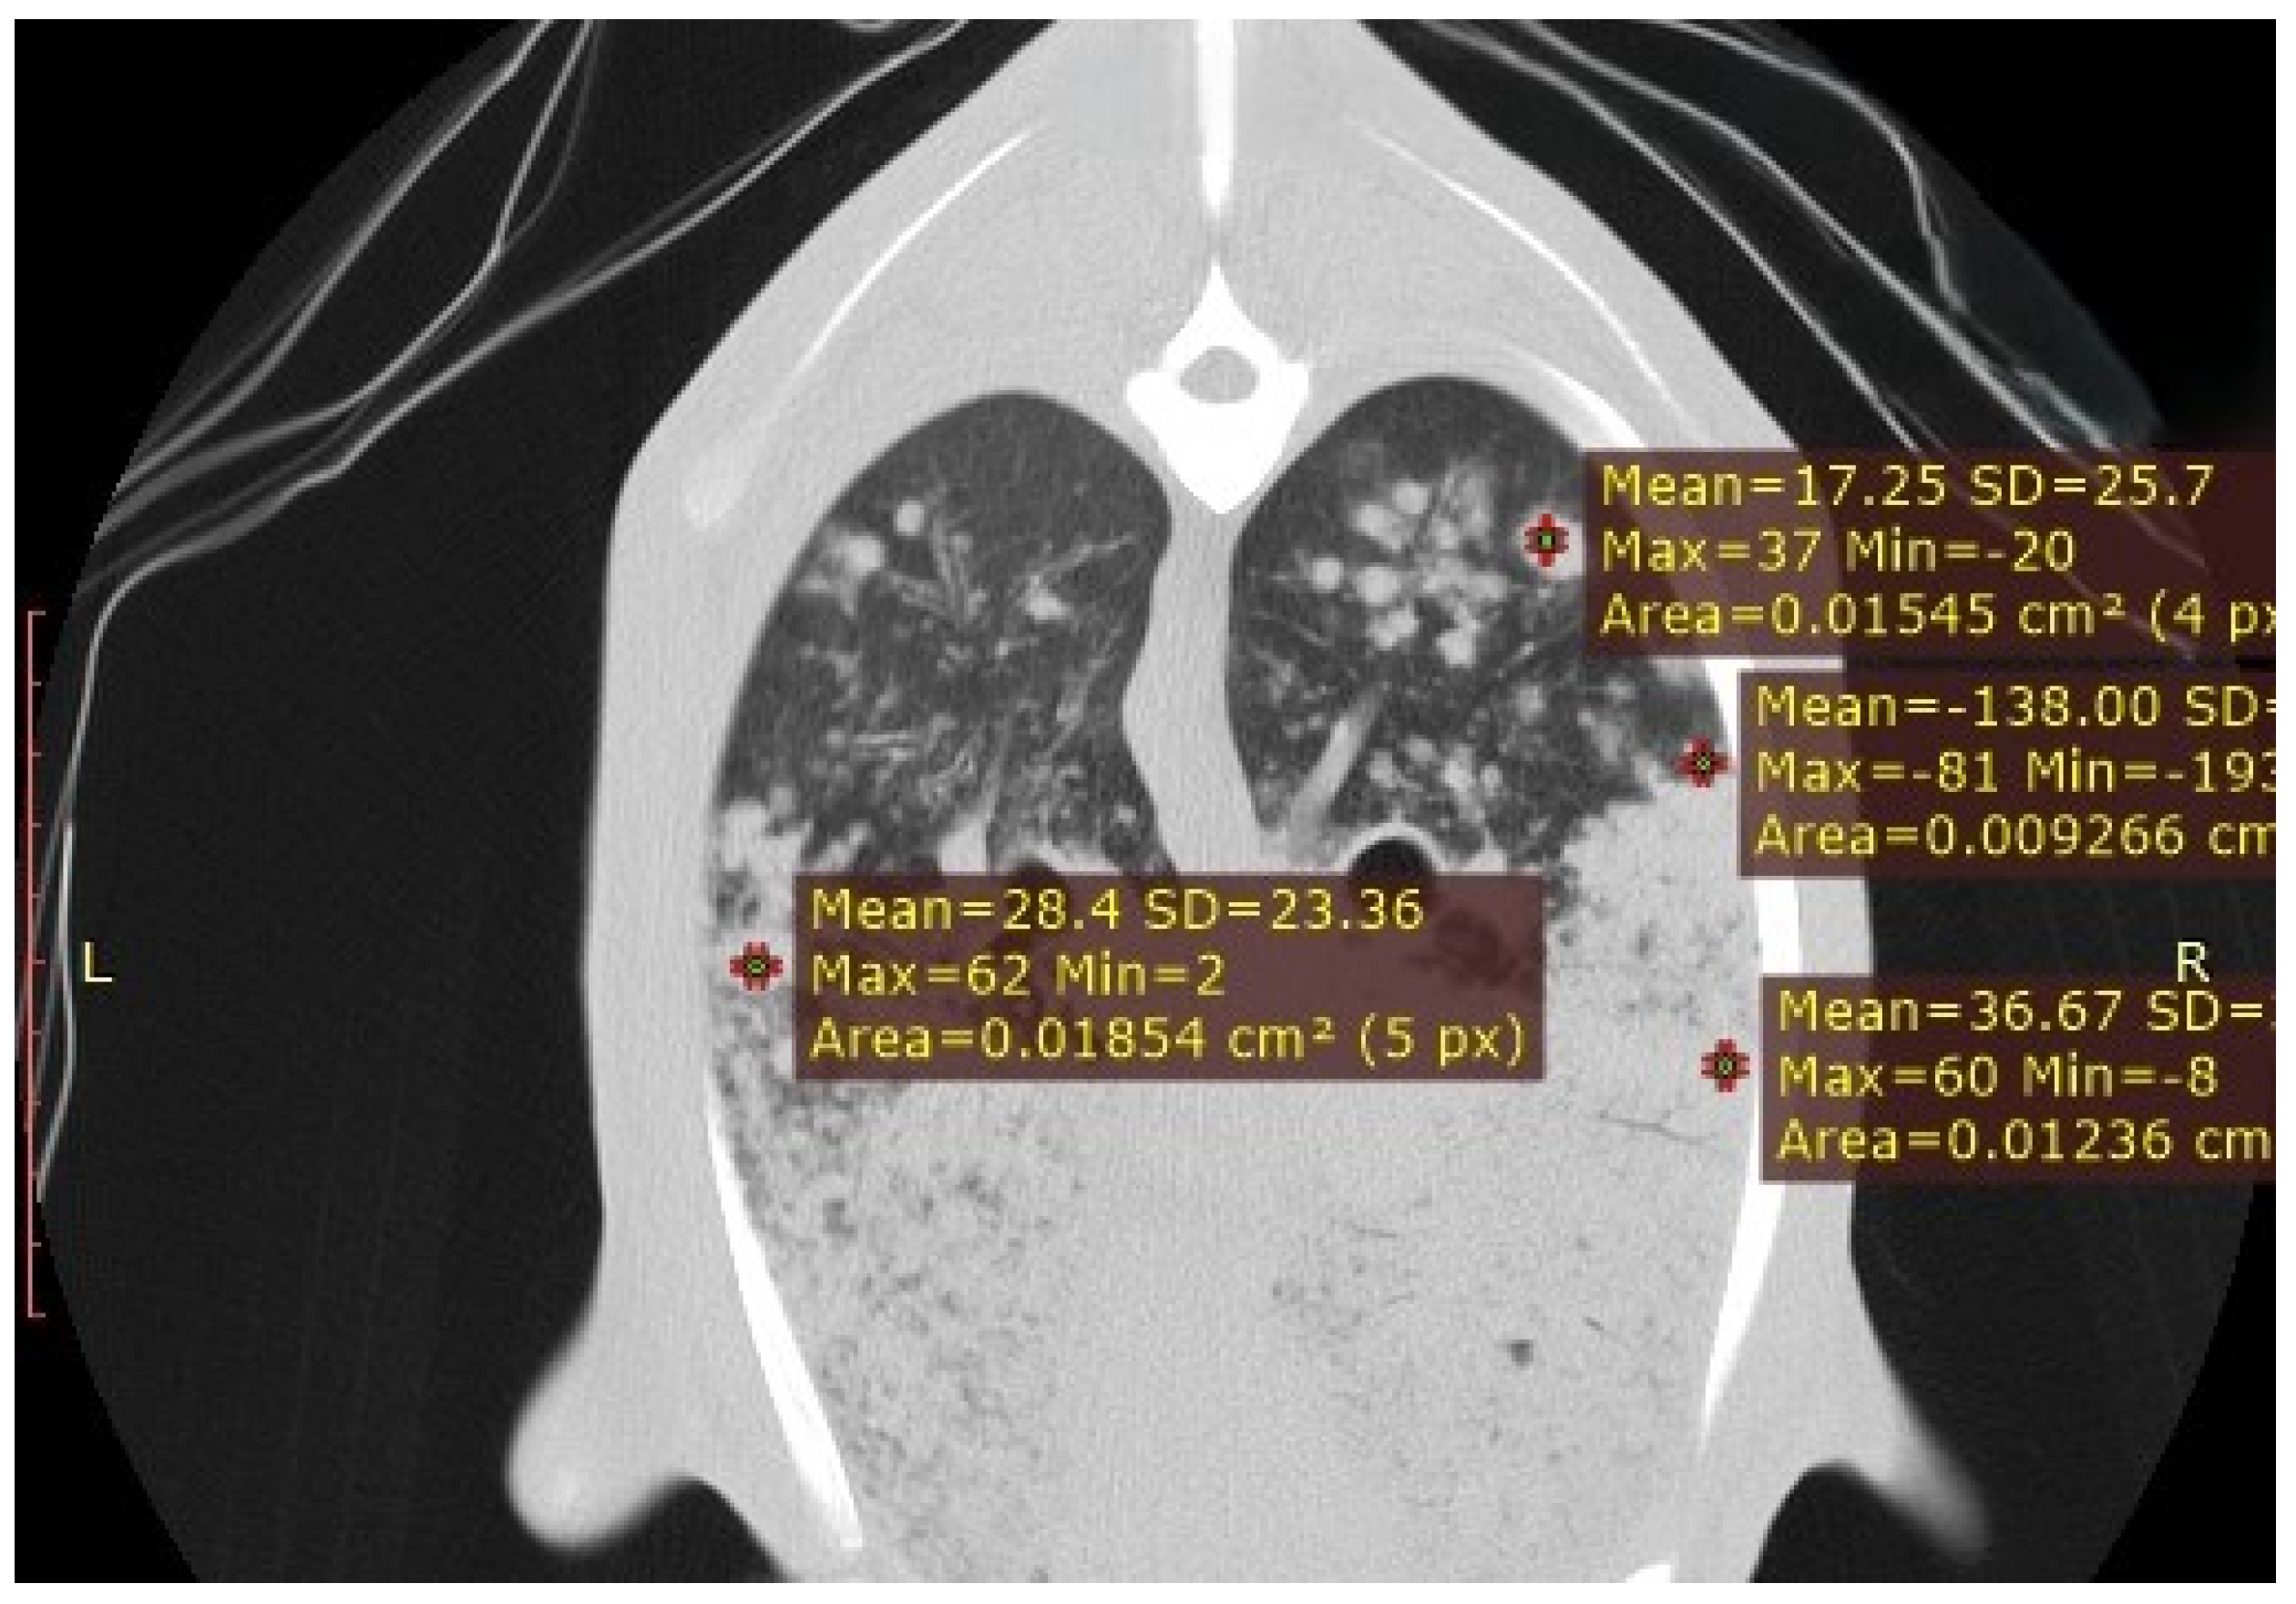

3.3.6. Ovine Pulmonary Adenocarcinoma (OPA)

| OPA | Primary masses with satellite nodules | −5 to −30 HU (primary), −90 to −200 HU (metastases) | Solid masses; differences in tissue composition between primary and metastatic lesions |